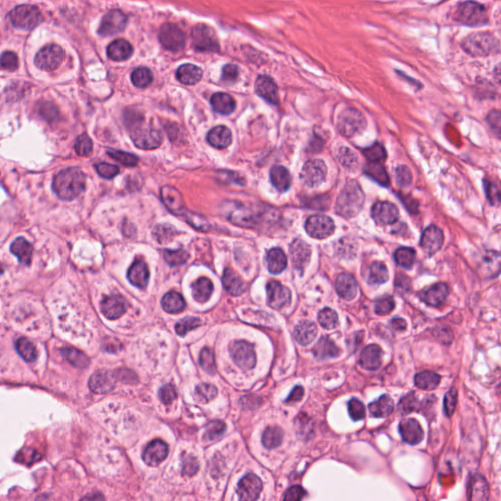

As an essential part of digital pathology, histopathology image analysis is playing increasingly important role in cancer diagnosis, which can provide direct and reliable evidence to diagnose the grade and type of cancer. This paper deals with nuclei segmentation, an important step in histopathological image analysis. The purpose of nuclei semgentation is not only counting the number of nuclei but also obtaining the detailed information of each nucleus. So unlike nuclei detection, here the outputs are the contour of each nucleus instead of only the position of their central points. Hence we can exactly extract each nucleus from the image and make it available for further analysis. For example, the features of the individual nucleus and the distribution of nuclei clusters can be used to grade and classify status of breast cancers [3, 4]. Because of appearance variation such as color, shape, and texture, nuclei segmentation from histopathological images could be very challenging, as illustrated in Fig.1, in which it is very challenging even for human to recognize and segment all nuclei within the images. Fig.1(a) and Fig.1(b) illustrate two histopathological images from different organs. Fig.1(c) and Fig.1(d) are two histopathological images from same organ but have different cancer grade.

Figure 6 shows how our method segments the nuclei step by step. The color variety is well controlled by the color normalization procedure. The prediction result shows clear nuclear areas and nucleus boundaries. In the final segmentation result and ground truth image, each nucleus is represented by a different color.